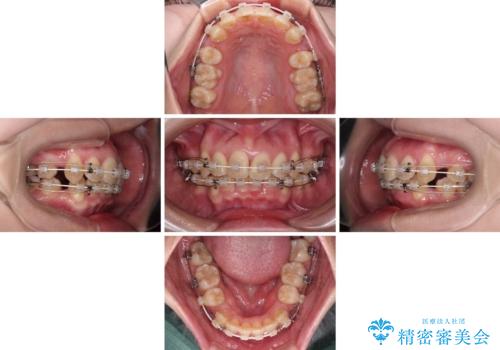

- 前歯のデコボコと突出感を気にして来院された患者様です。

上下左右第一小臼歯4本を抜歯して、積極的に口元を引っ込めるよう、ワイヤー装置にて矯正治療を行うこととしました。